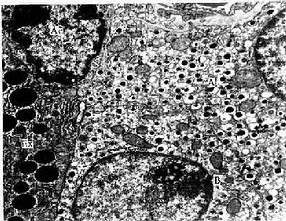

1.腺泡腺细胞呈锥体形,细胞底部位于基膜上,基膜与腺细胞之间无肌上皮细胞。腺细胞具有合成蛋白质的结构特点,基部胞质内含有丰富的粗面内质网和核糖体,故在HE切片上,此处胞质呈嗜碱性。细胞核圆形,位近基底部。细胞合成的蛋白质(酶的前体),经高尔基复合体组装于分泌颗粒(酶原颗粒)内。颗粒聚集于细胞顶部(图13-5),其数量因细胞功能状态不同而异,饥饿时细胞内分泌颗粒增多;进食后细胞释放分泌物,颗粒减少。

图13-5 小鼠胰腺细胞电镜像×12000

S分泌颗粒,RER粗面内质网,M线粒体,Lu腺腔,TJ紧密连接

(上海医科大学电镜室供图)